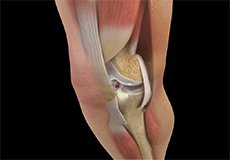

Knee Anatomy

The knee is a complex joint made up of different structures including bones, tendons, ligaments and muscles. They all work together to maintain normal function and provide stability to the knee during movement.